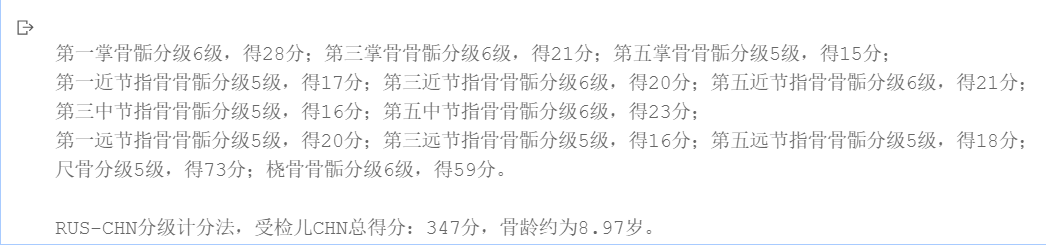

骨龄1